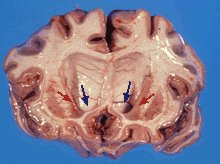

مرض هنتنجتونHuntington's disease هو اضطراب وراثي شديد في الجهاز العصبي. ويتسبب هذا المرض في تدمير خلايا الدماغ، كما يتسبب في حدوث حركات لا إرادية للجسم إلى جانب اضطراب عقلي تعقبه الوفاة. وهذا الاضطراب يصيب الناس من كلا الجنسين بصرف النظر عن العرق البشري. وأخذ هذا المرض اسمه من اسم أول من اكتشفه وهو جورج هنتنجتون الطبيب الأمريكي الذي كان أول من وصف هذا المرض في عام 1872م. وكانت هذه الحالة أصلا تسمى رَقَاص هنتنجتون.

وقد يكون أول الأعراض الجسمانية لهذا المرض تثاقلاً في الحركة أو عدم الحركة مطلقاً. ثم تبدأ بعد ذلك عضلات الوجه والأيدي في الارتعاش. وكلما زادت شدة المرض ازداد الانقباض العضلي اللا إرادي، وقد يصيب هذا الانقباض عضلات الجسم كلها. وبذلك يرتعش الرأس والكتفان والذراعان والساقان بطريقة غير إرادية. وعندما يسير المريض تتداخل الحركات الإرادية وغير الإرادية للجسم لينتج عنها ترنح في الجسم وخطوات تشبه إيقاع الرقص. وتشمل الأعراض العقلية المبكرة لهذا المرض الغباء، وتبلد الحسّ، وسرعة التهيج والتأثر، والإهمال في الهندام والمظهر الشخصي. ثم يعمل المرض على التدمير التدريجي لذكاء المريض ولذاكرته. وعندئذ قد يزداد المرض العقلي شدة.

وقد يفقد المريض أخيراً كل تحكم في العضلات وفي القدرة العقلية. وقد تحدث الوفاة نتيجة الالتهاب الرئوي أو الأزمة القلبية أو أي مضاعفات لهذا المرض.